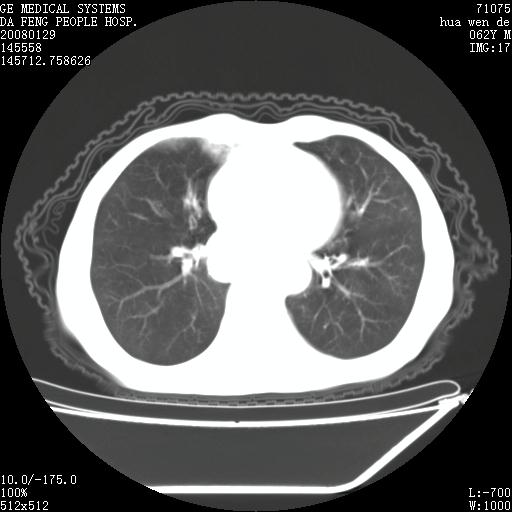

1.整个食管扩张,未见明显占位性病变,贲门区亦未见明显占位病变,考虑:贲门失驰缓症;

2.右上肺病变边缘可见毛刺,囊壁厚度不均匀,周围境界较清楚,未见炎性渗出性影,右上肺外带可见片状影,边缘不清,考虑:肺癌伴空洞形成、右上肺炎。

贲门失驰缓症.肺部感染伴脓肿形成。支持!是否吸入性要结合临床诊断,我们影像是看不出来的。但胸腔胃能排除(1.没有手术史支持,2.双侧胸廓对称,胸壁、肋骨及胸膜规整,3,食管壁明显扩张内壁光滑,胸腔胃黏膜皱襞多较厚)。

食管全程扩张,壁均匀不厚,喷门失弛缓症

右上肺空洞可见液平,临近肺野磨玻璃密度,考虑1.结核2.脓肿 支持!